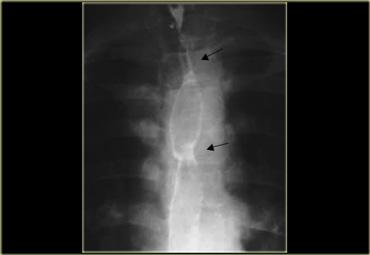

Hình ảnh của bệnh nhân mắc pemphigoid lành tính.

Các bóng nước niêm mạc đã dẫn đến hình thành nhiều đoạn hẹp (mũi tên).

Hình ảnh của bệnh nhân mắc ly thượng bì bọng nước lành tính.

Các đoạn hẹp đa ổ (mũi tên) là di chứng của bệnh lý bọng nước niêm mạc.

Bệnh lý bọng nước da lan rộng đã dẫn đến dính ngón tay và co rút.